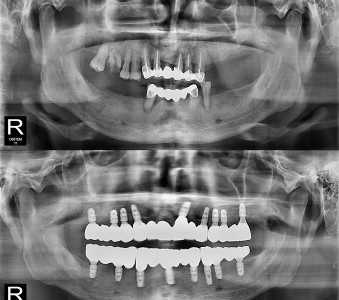

오스템 임플란트 프리미엄 BA 등급 사용

같은 오스템이라도 등급이 다릅니다. 더 빠른 골유착을 위해 프리미엄 등급을 사용합니다.

결과로 증명합니다.

국제모아치과의

실제 임상 증례